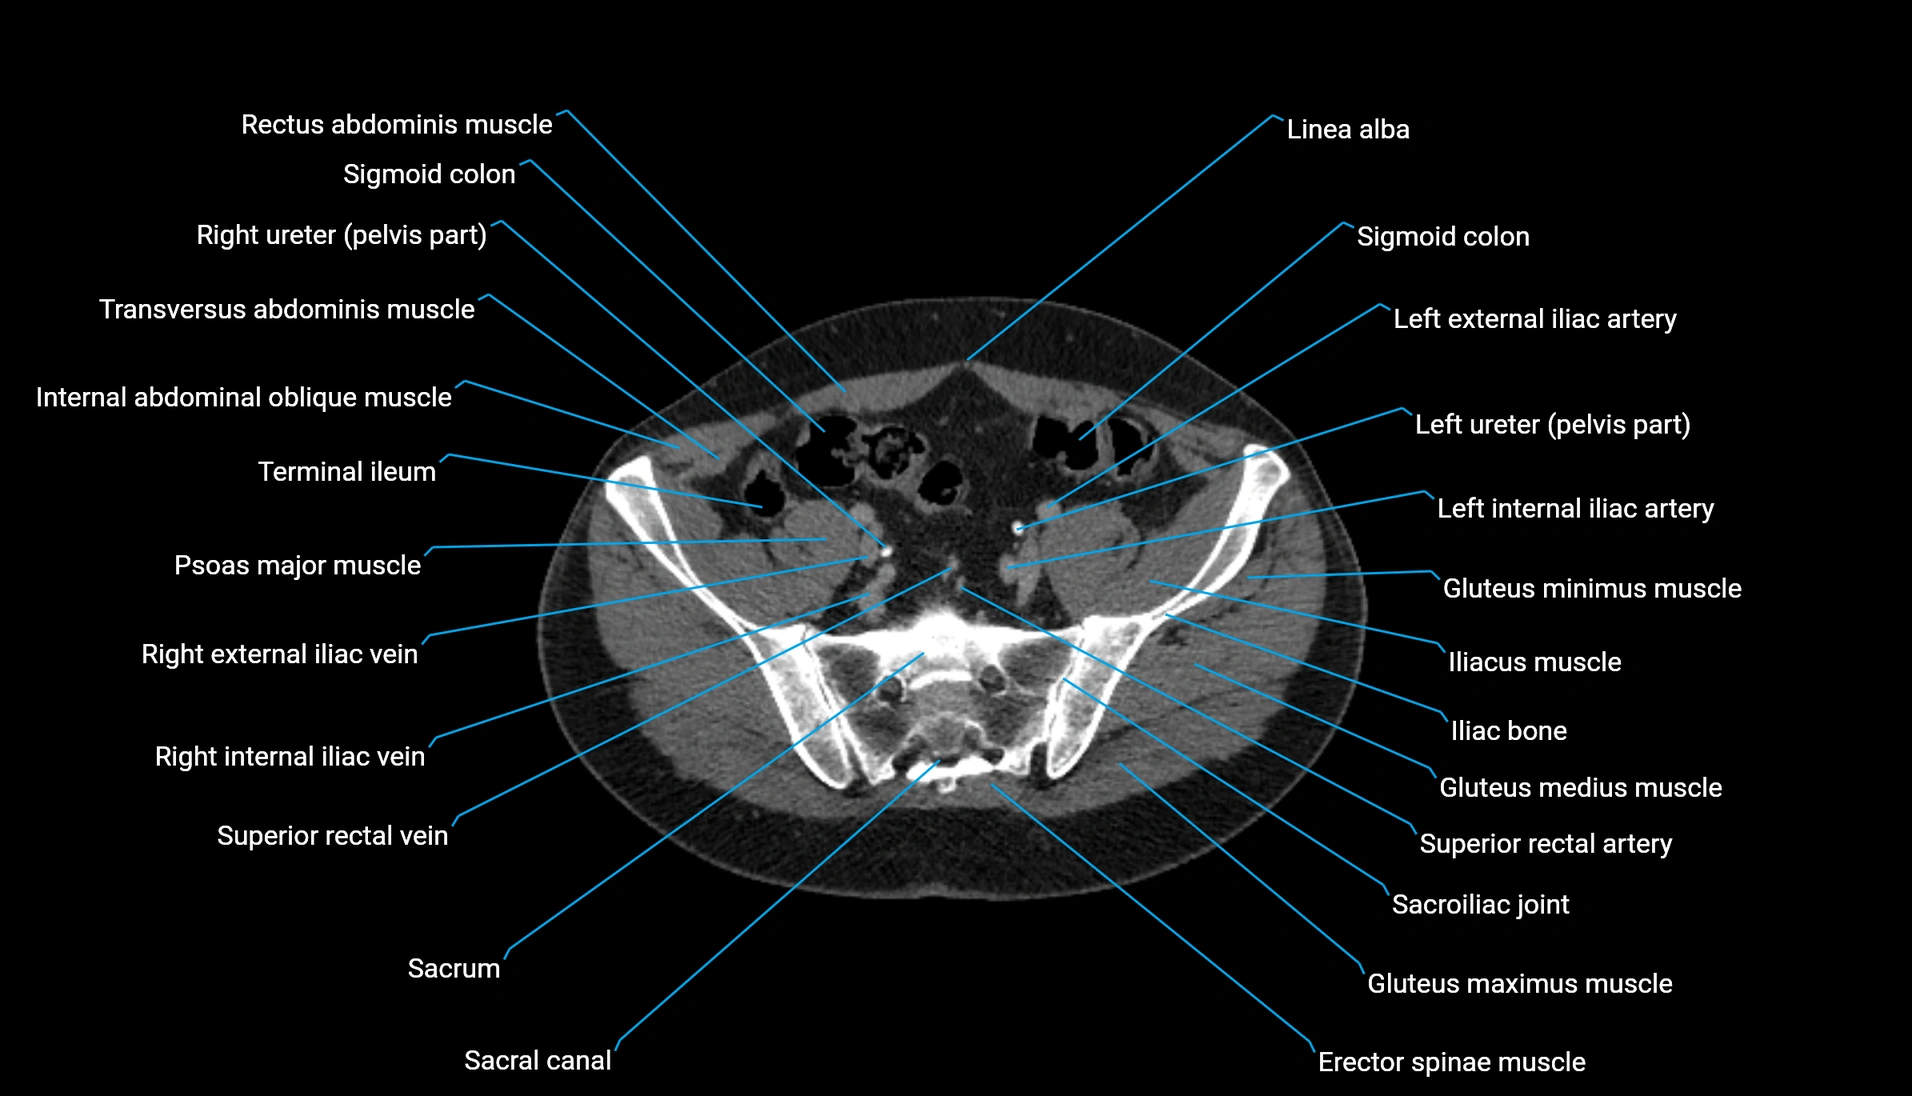

CT Appearance

Non-contrast CT:

-

Demonstrates cortical bone of acetabular rim in excellent detail

Detects fractures, dysplasia, retroversion, or bony overcoverage (pincer impingement)

3D reconstructions used in preoperative hip surgery planning

CT VRT 3D image

CT image